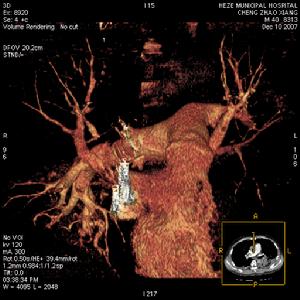

发生率约75%。开始于缺氧导致的呼吸急促及随后的过度换气,紫绀有时不会出现,但有时可能成为FES的早期体征。涉及肺的FES病人大部分PaO2水平低于6.67kPa,如果肺的条件恶化,就可能合并呼吸困难和代谢性酸中毒。部分病人有咯血。胸部X线片示两肺大块斑片状阴影,称之为“暴风雪样”改变,尤其在肺的上中部多见。

1.主要标准 (1)皮下出血:可在伤后2~3天左右,双肩前部、锁骨上部、前胸部、腹部等皮肤疏松部位出现,也可见于结膜或眼底,伤后1~2天可成批出现,迅速消失,可反复发生。因此,对骨折病人入院数天内应注意检查。 (2)呼吸系统症状:主要症状为呼吸困难、咳嗽、咳痰(经常有血性),但湿性啰音不是特有症状。典型肺部X线可见全肺出现“暴风雪”状阴影,并常有右心负荷量增加的影像。但这种阴影不一定都能发现,而且如无继发感染,可以很快消失。因此,对可疑病例,可用轻便X线机反复检查。 (3)脑症状:主要表现为头痛、不安、失眠、兴奋、谵妄、错乱、昏睡、昏迷、痉挛、尿失禁等症状。虽很少出现局灶性症状,但偶然可有斜视、瞳孔不等 大及尿崩症等,因此,当有些骨折病例出现难以解释的脑症状时,应怀疑脂肪栓塞。